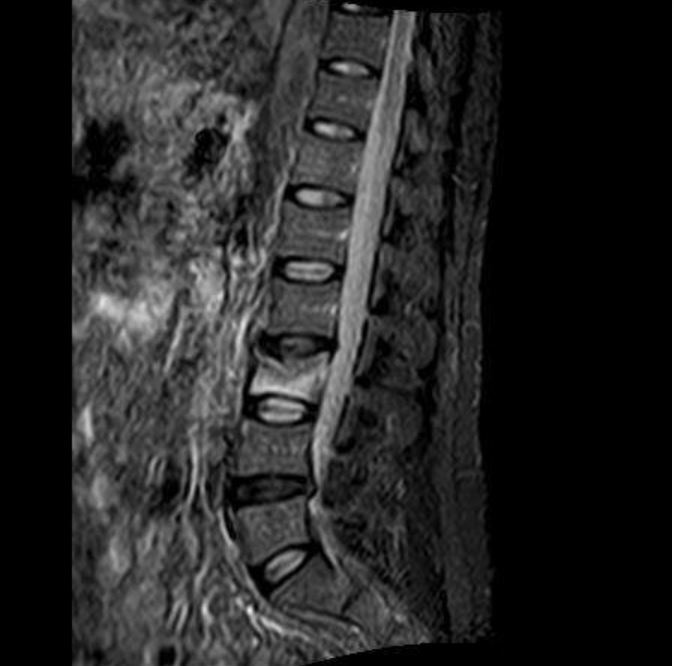

Q

what is this and what is it called?

risk factor? why?

A

wedge # of L3

osteoporosis - trabecular bone